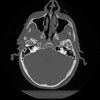

12 P.BLANDAS,,Vol,0.5,P.BLANDAS,,